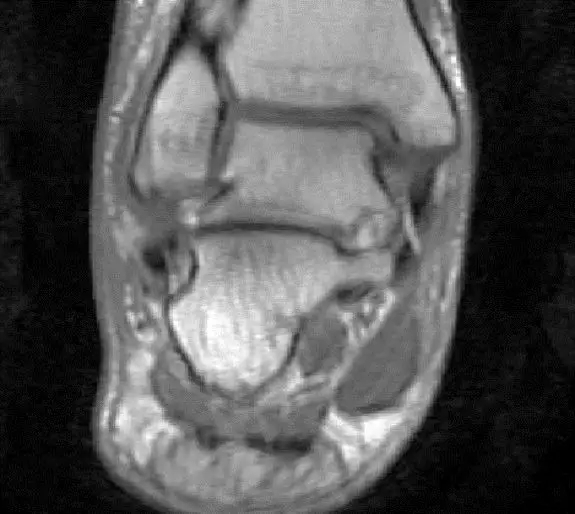

此片可以看到距腓前韧带和跟绯韧带有高信号大片的渗出病变,韧带结构松弛,增粗,这个地方可以看到腓骨前韧带的segond骨折块,所以考虑是踝关节外侧副韧带损伤,腓骨腱的segond骨折。